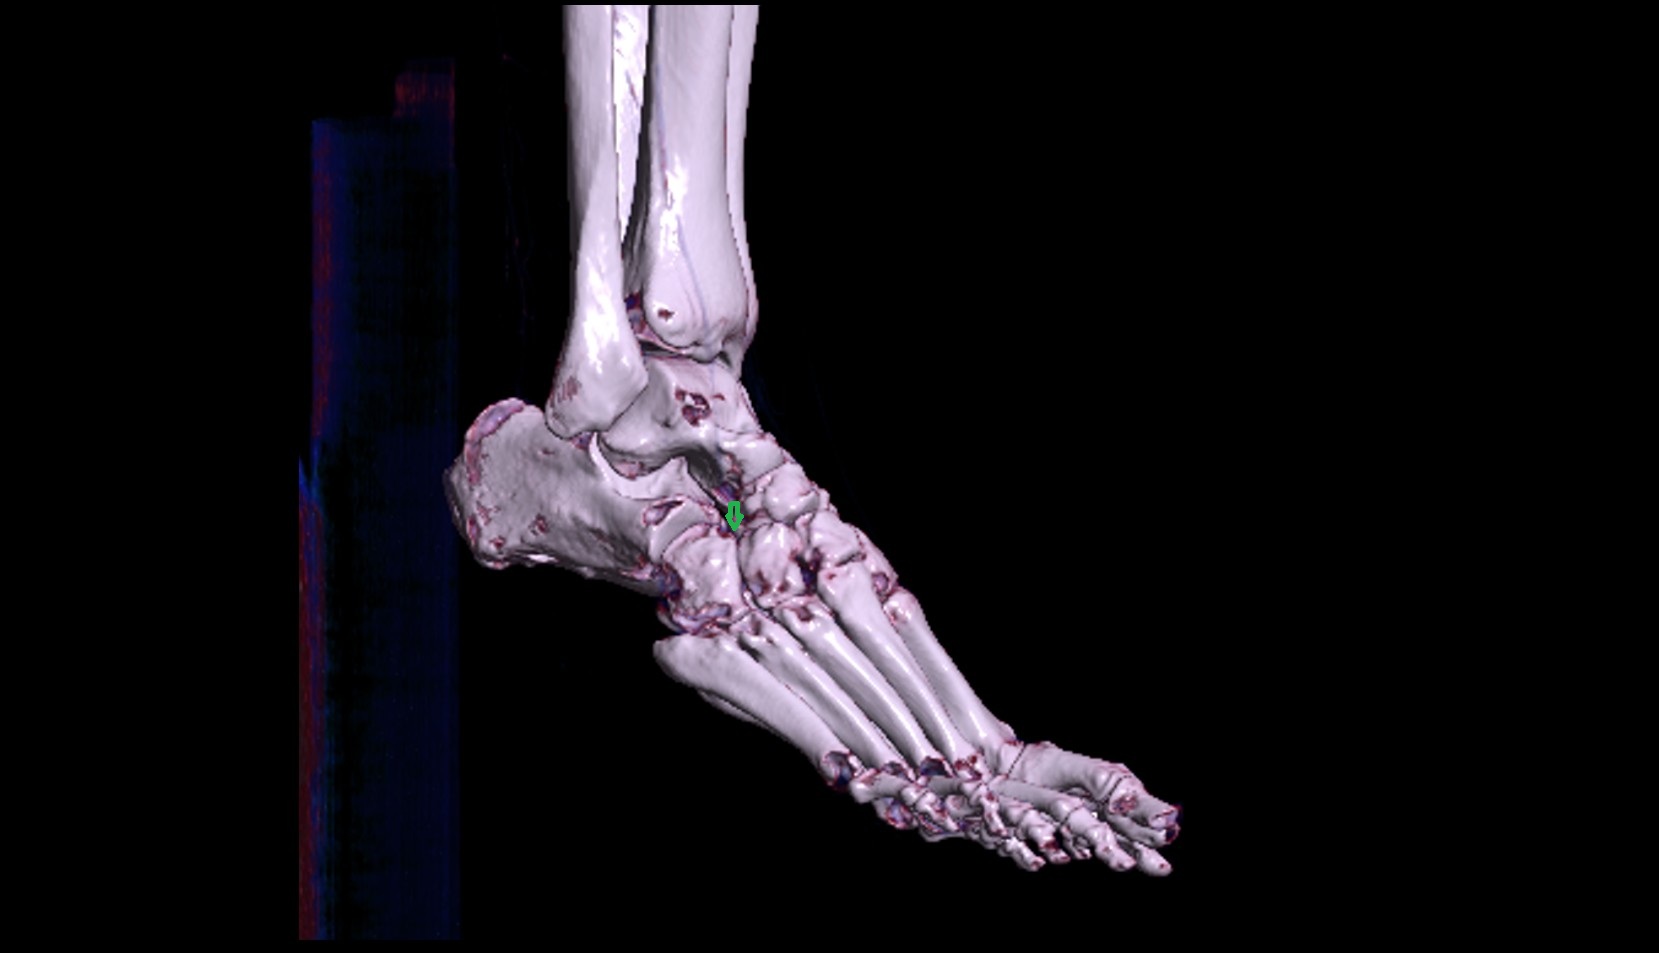

- Talus

- Head of talus

- Body of talus

- Neck of talus

- Calcaneus

- Cuboid

- Fibula shaft

- Medial malleolus

- Lateral malleolus

- Ankle joint

- Talocalcaneal joint

- Talocalcaneonavicular joint

- Calcaneocuboid joint

- Lateral cuneiform bone

- Medial cuneiform bone

- Intermediate cuneiform bone

- Interosseous membrane (middle tibiofibular ligament)

- Navicular bone